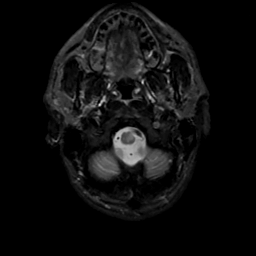

MR Study #8, March 31, 1991 -- Slice #3

[Home][Help][Clinical][Tour 1][Tour 2] Slice 3